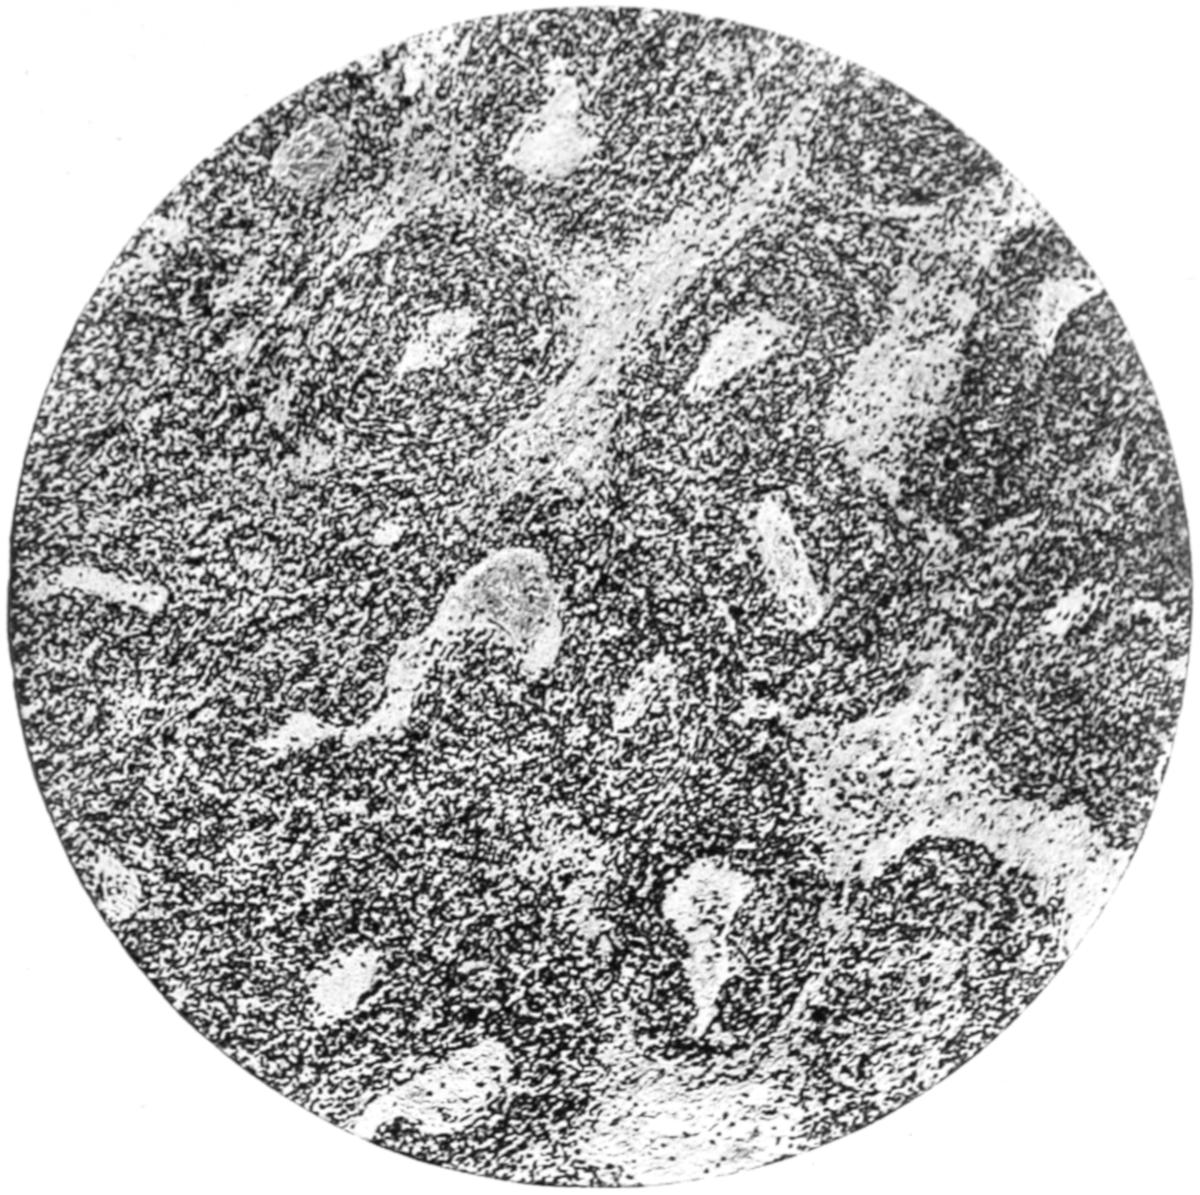

The value of a careful blood examination is well illustrated by Plate I, prepared by Dr. Irving P. Lyon, in which are displayed the alterations of greatest interest to the surgeon.

PLATE I

Fig. I.

Fig. II.

Fig. III.

Fig. IV.

Fig. V.

Fig. VI.

Fig. VII.

Fig. VIII.

DRAWN BY J. N. Z. CHASE

PLATE I.

BLOOD.

(Ehrlich triple stain.)

(Prepared by Dr. I. P. Lyon.)

Fig. I. TYPES OF LEUCOCYTES.

a. Polymorphonuclear Neutrophile. b. Polymorphonuclear Eosinophile. c. Myelocyte (Neutrophilic). d. Eosinophilic Myelocyte. e. Large Lymphocyte (large Mononuclear). f. Small Lymphocyte (small Mononuclear).

Fig. II. NORMAL BLOOD.

Field contains one neutrophile. Reds are normal.

Fig. III. ANÆMIA, POST-OPERATIVE (secondary).

The reds are fewer than normal, and are deficient in hæmoglobin and somewhat irregular in form. One normoblast is seen in the field, and two neutrophiles and one small lymphocyte, showing a marked post-hæmorrhagic anæmia, with leucocytosis.

Fig. IV. LEUCOCYTOSIS, INFLAMMATORY.

The reds are normal. A marked leucocytosis is shown, with five neutrophiles and one small lymphocyte. This illustration may also serve the purpose of showing the leucocytosis of malignant tumor.

Fig. V. TRICHINOSIS.

A marked leucocytosis is shown, consisting of an eosinophilia.

Fig. VI. LYMPHATIC LEUKÆMIA.

Slight anæmia. A large relative and absolute increase of the lymphocytes (chiefly the small lymphocytes) is shown.

Fig. VII. SPLENO-MYELOGENOUS LEUKÆMIA.

The reds show a secondary anæmia. Two normoblasts are shown. The leucocytosis is massive. Twenty leucocytes are shown, consisting of nine neutrophiles, seven myelocytes, two small lymphocytes, one eosinophile (polymorphonuclear) and one eosinophilic myelocyte. Note the polymorphous condition of the leucocytes, i. e., their variations from the typical in size and form.

Fig. VIII. VARIETIES OF RED CORPUSCLES.

a. Normal Red Corpuscle (normocyte). b, c. Anæmic Red Corpuscles. d-g. Poikilocytes. h. Microcyte. i. Megalocyte. j-n. Nucleated Red Corpuscles. j, k. Normoblasts. l. Microblast. m, n. Megaloblasts.